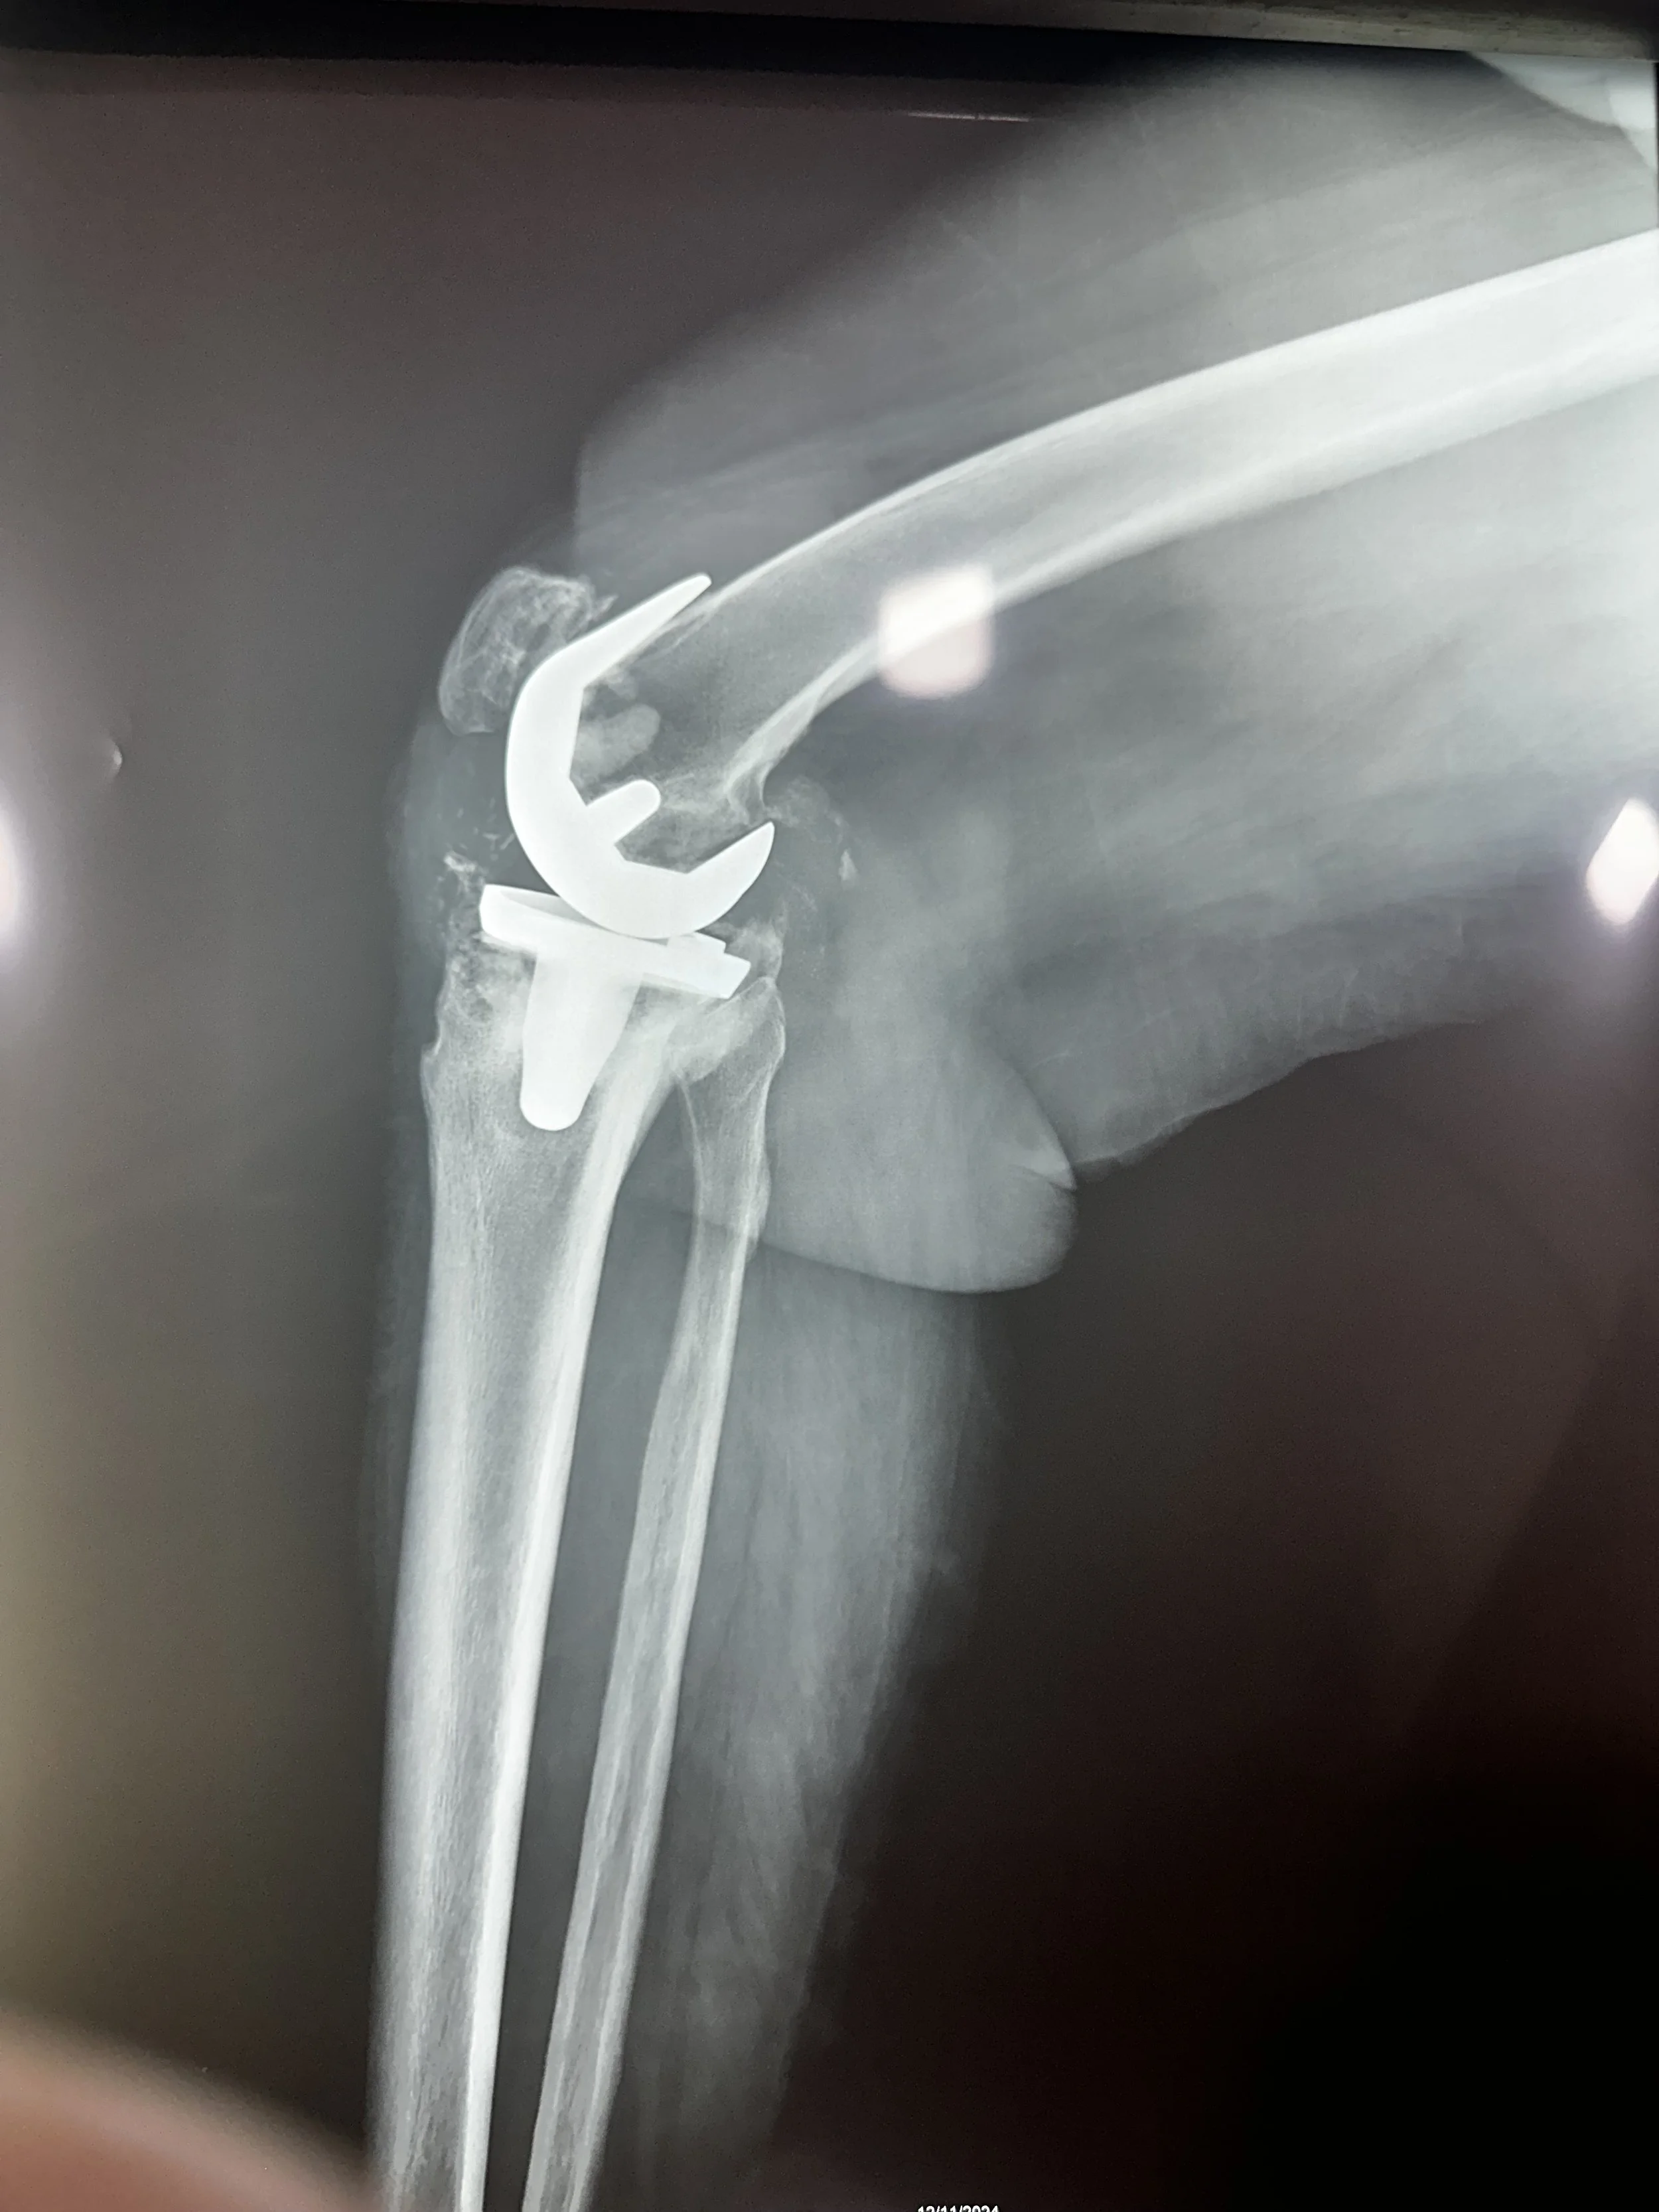

Once back at the hospital, everyone jumped into their positions, with five operating rooms running simultaneously. By the end of the day, the team had performed 24 procedures, including 7 total hips, 13 total knees, and 4 foot & ankle. From a warm word of assurance and prayer during pre-op to the professional teamwork in surgery to the gentle hand guiding in recovery, every Team HIM member performed their responsibilities with passion, joy, and diligence.